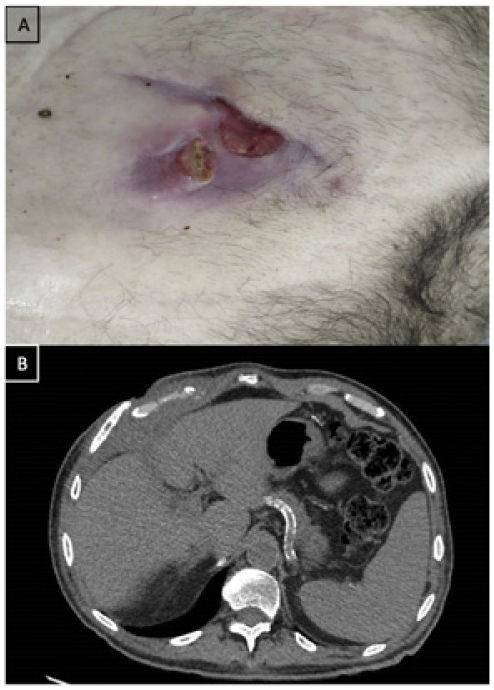

We report the case of a patient presented to hospital with progressive worsening of wound at lower right thoracic wall (Fig. 1A) secondary to chest trauma and displaced rib fractures (Fig. 1B). During chest wall repairing surgery, cholecystocutaneous fistula and gallstones were evidenced (Fig. 2A). No previous hepatobiliary history was documented. Cholecystectomy was performed with subsequent repair of the chest wall by latissimus dorsi myocutaneous flap (Fig. 2B).